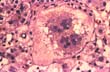

Multinucleation

Fig 65 - In certain inflammatory and necrotic processes regenerating hepatocytes become highly multinucleated. This phenomenon is seen especialy in children. This slide shows a hepatocyte with more than 20 nuclei in a case of so-called "neonatal hepatitis".